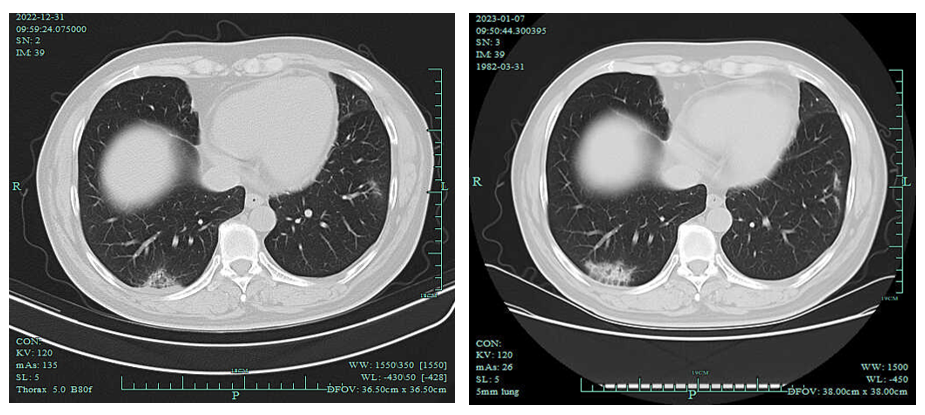

2022-12-31胸部增强CT:左上肺癌治疗后复查,对照2022-11-17CT肿块稍缩小,纵隔及邻近多发血管受侵情况较前略好转。两肺下叶炎症,较前新发,建议治疗后复查。原前纵隔结节已消失。心包少量积液。右侧心膈淋巴结稍大,较前片大致相仿。

2、2023-01-07胸部CT:两肺下叶炎症,较前2022-12-31CT略进展,建议治疗后复查。

左上肺癌治疗后复查,较前相仿。心包少量积液。右侧心膈淋巴结稍大,较前片相仿。

影像学检查图像(2022-12-31和2023-01-07肺部病灶变化)